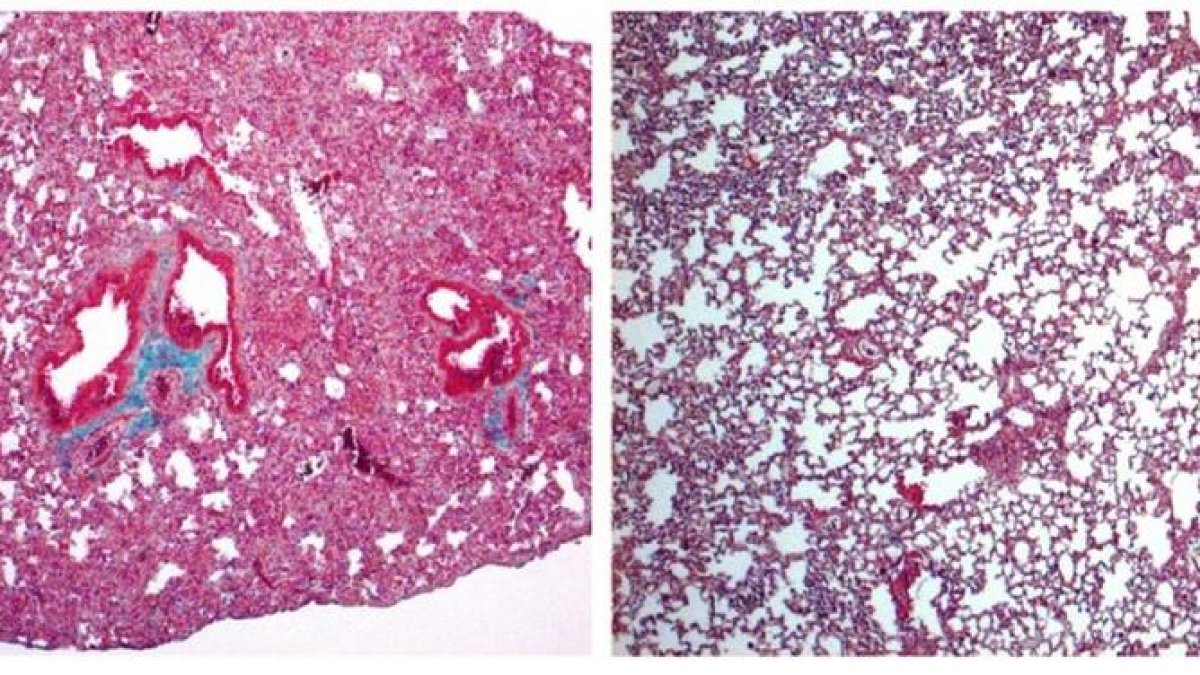

El estudio, realizado en modelos animales, se publica en British Journal of Pharmacology y, entre las enfermedades a tratar asociadas a la fibrosis pulmonar estarían el daño pulmonar agudo y su forma más severa, el síndrome de dificultad respiratoria aguda.

Los investigadores han demostrado que la falta de cortistatina provoca una respuesta descontrolada y nociva del sistema inmunitario -la tormenta de citoquinas- y el posterior desarrollo de la reacción fibrótica pulmonar.

Por contra, el tratamiento con cortistatina protege frente a las formas graves de daño pulmonar agudo y el síndrome de dificultad respiratoria aguda, señala un comunicado del Consejo Superior de Investigaciones Científicas (CSIC), que indica que esta característica la convierte en una candidata para tratar la fibrosis más grave causada por la covid-19.

Aunque los estudios anteriores reconocían la cortistatina como un potente agente antiinflamatorio, este es el primero que identifica su capacidad para regular y revertir directamente la respuesta fibrótica crónica.